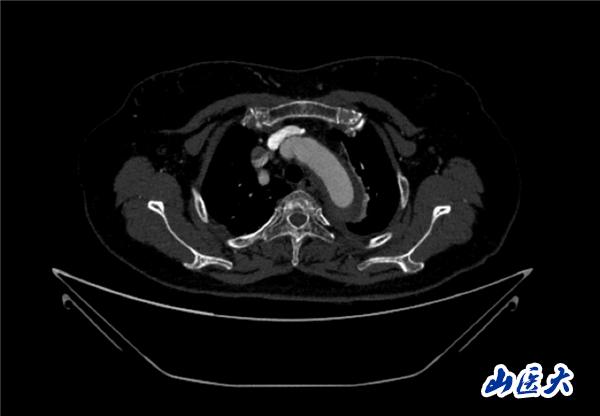

首例患者是一位55歲的女性,她患有高血壓約2年時(shí)間,平時(shí)也會(huì)規(guī)律服用多種降壓藥,但血壓控制始終不盡人意。2023年4月下午,她出現(xiàn)不明原因的頭痛,在家拔罐緩解少許便未到醫(yī)院就醫(yī),次日凌晨突感胸悶、胸背疼痛伴有呼吸困難等癥狀、家人急忙撥打了120,把患者送入醫(yī)院急診科進(jìn)行救治,醫(yī)生在急診科行胸腹主動(dòng)脈CTA時(shí),顯示主動(dòng)脈弓部-降主動(dòng)脈及腹主動(dòng)脈壁間血腫,遂收治入醫(yī)院血管外科,患者入院10天后復(fù)查血腫仍未有改善,依然伴有胸背部疼痛等不適,如不進(jìn)一步處理,可能發(fā)展為夾層危及生命,患者及家屬經(jīng)過(guò)與醫(yī)生團(tuán)隊(duì)了解溝通,決定進(jìn)行創(chuàng)傷小、恢復(fù)快的介入手術(shù)治療。張瑋教授、符偉國(guó)教授、董紅霖教授及其血管外科團(tuán)隊(duì)(閆盛、常文凱、田琴琴)共同商討手術(shù)方案,最終確定使用Zipper?一體式主動(dòng)脈弓覆膜支架系統(tǒng),行胸主動(dòng)脈覆膜支架腔內(nèi)隔絕術(shù)+無(wú)名動(dòng)脈、左頸總動(dòng)脈、左鎖骨下動(dòng)脈分支重建術(shù)為患者進(jìn)行治療。董紅霖教授及其血管外科團(tuán)隊(duì)根據(jù)患者術(shù)前頭顱CT平掃提示雙側(cè)側(cè)腦室旁缺血灶,血壓控制不穩(wěn)定,屬夾層壁間血腫非典型夾層等風(fēng)險(xiǎn)點(diǎn),制定了完整的手術(shù)方案,術(shù)中經(jīng)股動(dòng)脈置入Zipper支架主體,經(jīng)預(yù)留導(dǎo)絲超選無(wú)名動(dòng)脈,并確保主體支架對(duì)位準(zhǔn)確,順利置入左頸總動(dòng)脈、左鎖骨下動(dòng)脈支架,重建弓上三分支。手術(shù)過(guò)程非常順利。術(shù)后觀察主動(dòng)脈及分支覆膜支架定位準(zhǔn)確;無(wú)內(nèi)漏;分支支架通暢,動(dòng)脈供血正常。

術(shù)前CTA